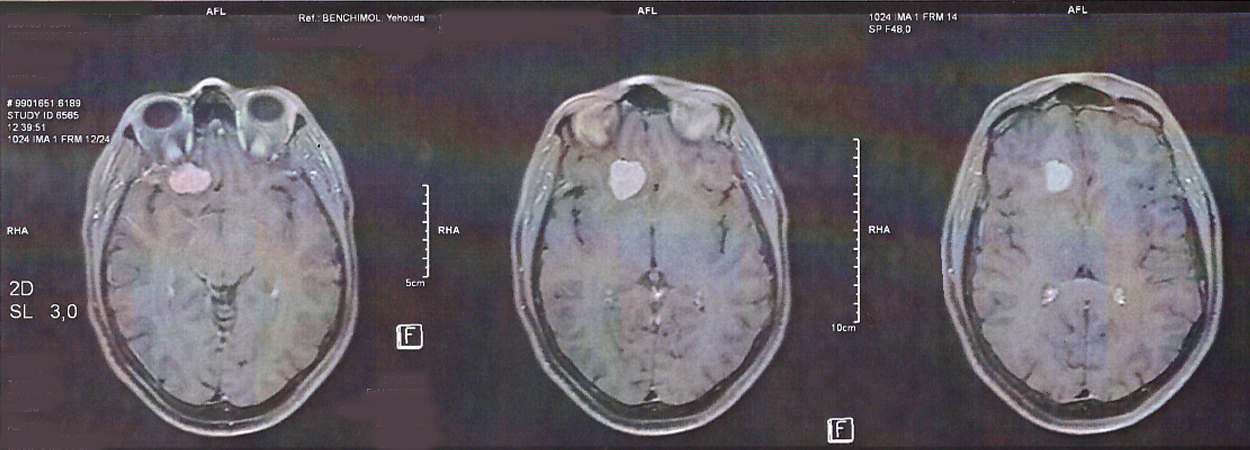

Méningiome cérébral découvert à l'IRM chez femme traitée par Lutényl

L’acétate de chlormadinone et l’acétate de nomégestrol sont des médicaments dérivés de la progestérone. Ces traitements ont été couramment utilisés dans la prise en charge de la ménopause, des troubles menstruels et de l’endométriose. Le méningiome est une tumeur, le plus souvent bénigne, qui se développe à partir des membranes qui enveloppent le cerveau et la moelle épinière (les méninges).

Compte-tenu du sur-risque démontré de méningiome associé à la prise d’acétate de nomégestrol (Lutényl et génériques) et d’acétate de chlormadinone (Lutéran et génériques), les recommandations de l'ANSM (Agence Nationale de Sécurité du Médicament et des produits de santé) sont exposées dans cet article.